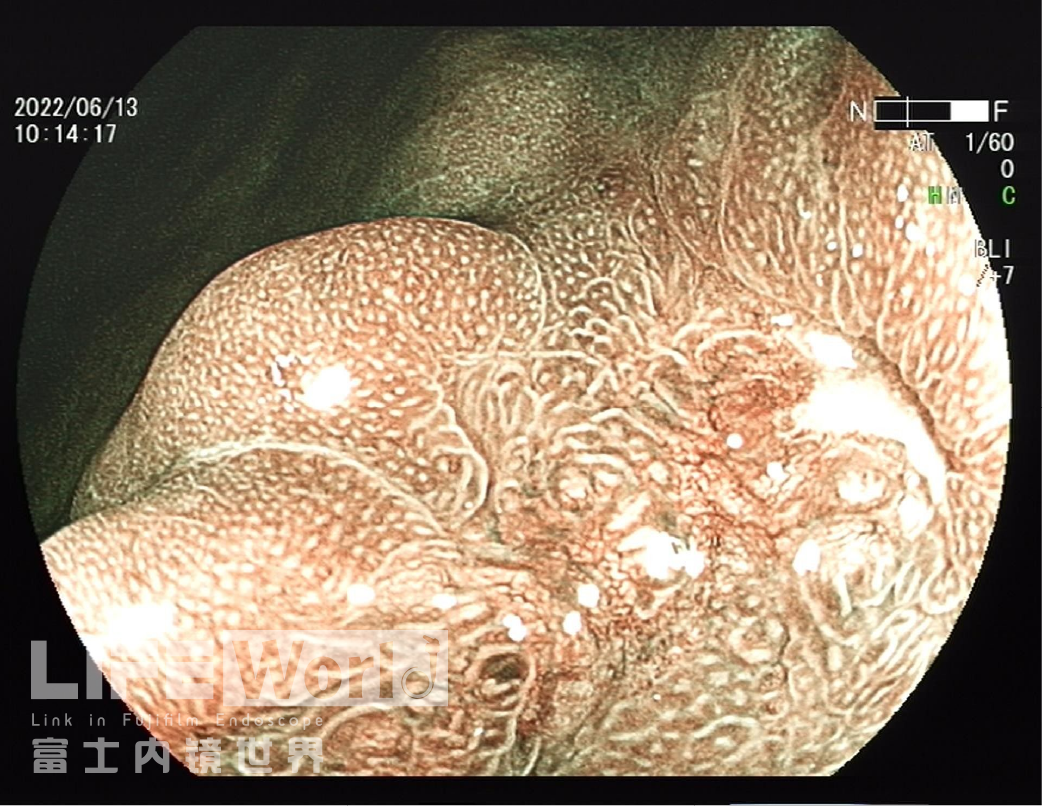

BLI模式低倍放大观察,可清晰的勾勒出病变的范围,病变的口侧端表面微结构的异型性明显,考虑为癌灶,病变的肛侧端异型性不明显,考虑为上皮内瘤变。

对考虑为癌灶的区域进行中倍放大观察:IMSP(+), IMVP(+)。

对考虑为癌灶的区域进行高倍放大观察,根据下面的胃癌放大内镜诊断流程图来进行判断。

LCIBLI+ME观察更好的呈现了病变的边界,微腺管及微血管结构变化,看到了白色球状物,喷洒醋酸后部分区域见绒毛状结构更清晰,通过LCIBLI+ME对病变的性质做出了早期癌的预判,操作过程精细规范,展示了一个精彩病例。

3、BLI放大下,口侧有明显的边界,有不规则的表面微结构和血管构造,考虑癌。有白色球状物,多见于分化型癌。腺体融合、血管构造不规则的树枝状,局部表面微结构显示不清,这些都支持中分化癌。